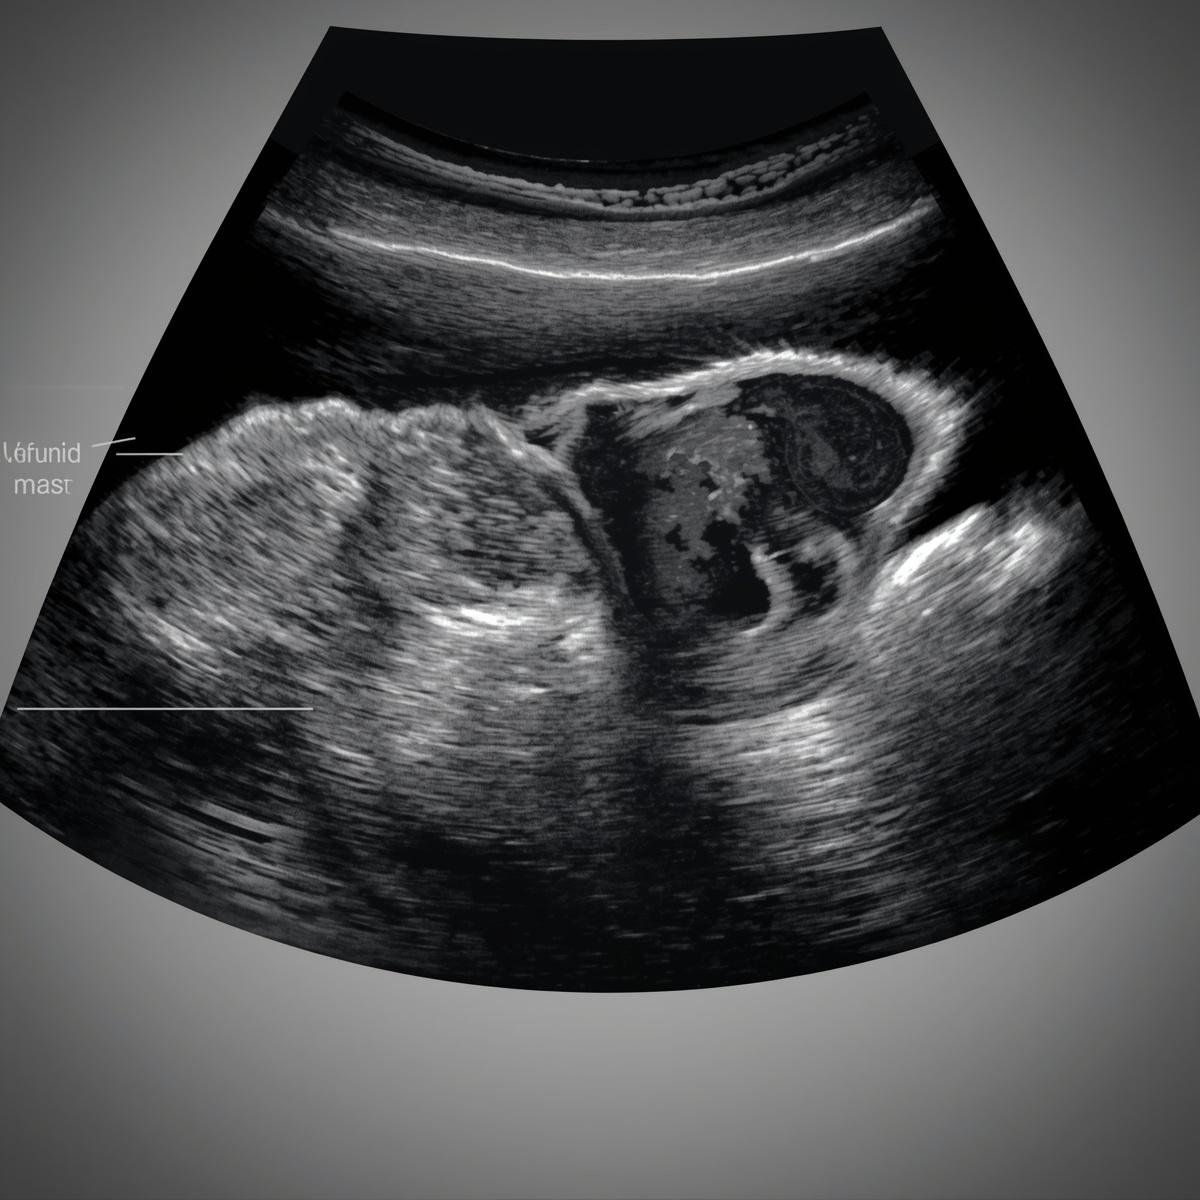

What is Gynae Surgery?

Gynae surgery involves surgical procedures used to treat conditions affecting the female reproductive system, such as the uterus, ovaries, and fallopian tubes. It is performed to manage problems like fibroids, ovarian cysts, and other gynecological conditions. Modern surgical techniques help ensure safe treatment and faster recovery for patients.

Surgery performed to remove cysts from the ovaries while maintaining healthy ovarian tissue.

Laparoscopic Gynecological Surgery

A minimally invasive procedure using small incisions and a camera for faster recovery and less pain.